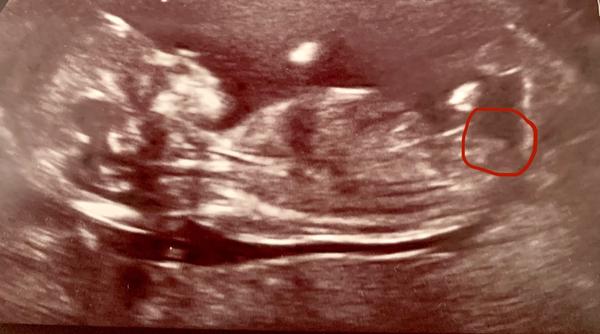

Pohlavní hrbolek na ultrazvuku. Jak ho poznat?